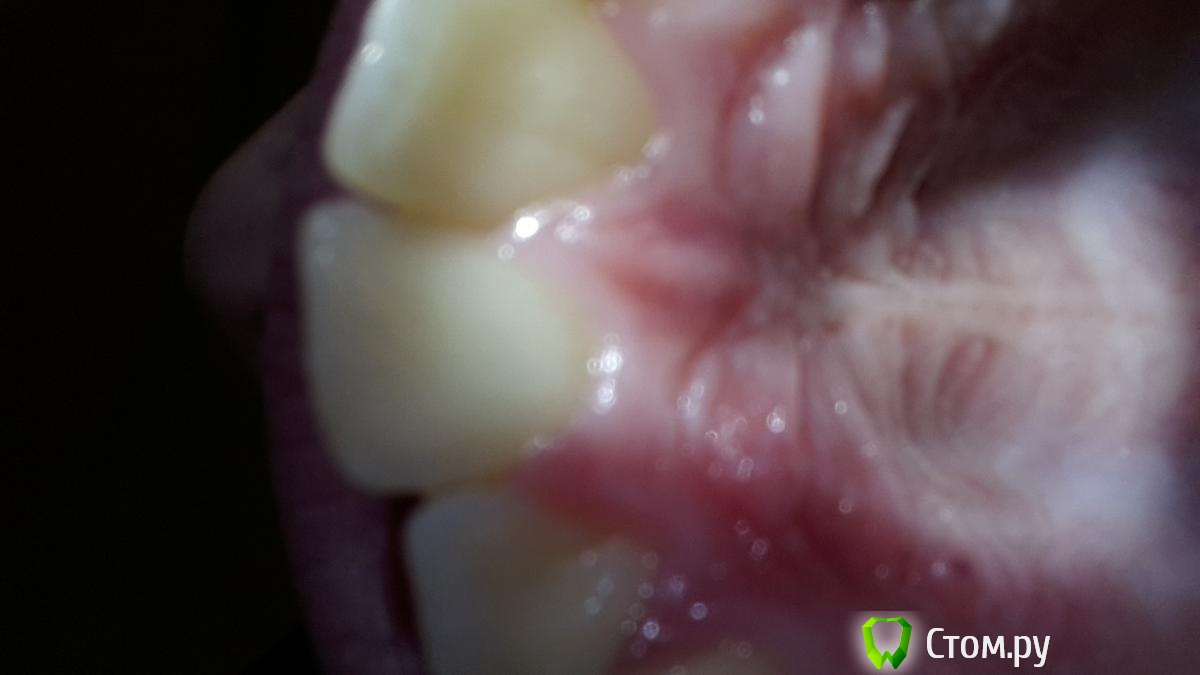

Romanur Опубликовано 19 декабря, 2013 Автор Поделиться Опубликовано 19 декабря, 2013 На фото верхняя часть нёба Ссылка на комментарий

Romanur Опубликовано 19 декабря, 2013 Поделиться Опубликовано 19 декабря, 2013 Что делать? Болит нёбо когда трогаешь языком или когда ешь твердую пищу. Мама сказала что у меня может быть киста. Страшно. Не помню обжигался или нет, ну вроде бы чай хлебнул кипяток) позавчера (может и не обжогся, не помню) Ссылка на комментарий

IvanK Опубликовано 19 декабря, 2013 Поделиться Опубликовано 19 декабря, 2013 Здравствуйте,думаю, что травма (обожглись)нужно просто подождать, пройдет для успокоения - выложите панорамный снимок (ОПТГ) Ссылка на комментарий